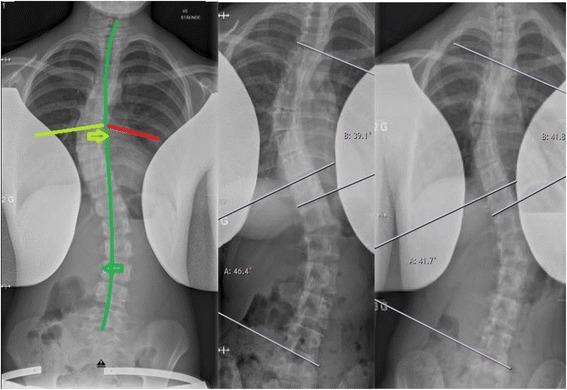

Nine patients with AIS were injected one time with ITB using ultrasonic and EMG guidance in the selected spine muscles. Radiographic and clinical examinations were performed before and 6 weeks after the injection. Primary outcome parameters of radiological changes were analyzed using Wilcoxon signed-rank test and binomial test, and secondary outcome parameters of short- and long-term clinical effects were obtained.

Significant radiological corrective changes were seen in the frontal plane in the thoracic and lumbar spine as well as significant derotational corrective change in the lumbar spine according to Cobb's angle measurements and to Nash and Moe's classification, respectively. No serious adverse events were detected at follow-up.

In conclusion, this study demonstrated that the psoas major muscle do play a role into the pathology in adolescent idiopathic scoliosis by maintaining the curvature of the lumbar spine and thoracic spine.